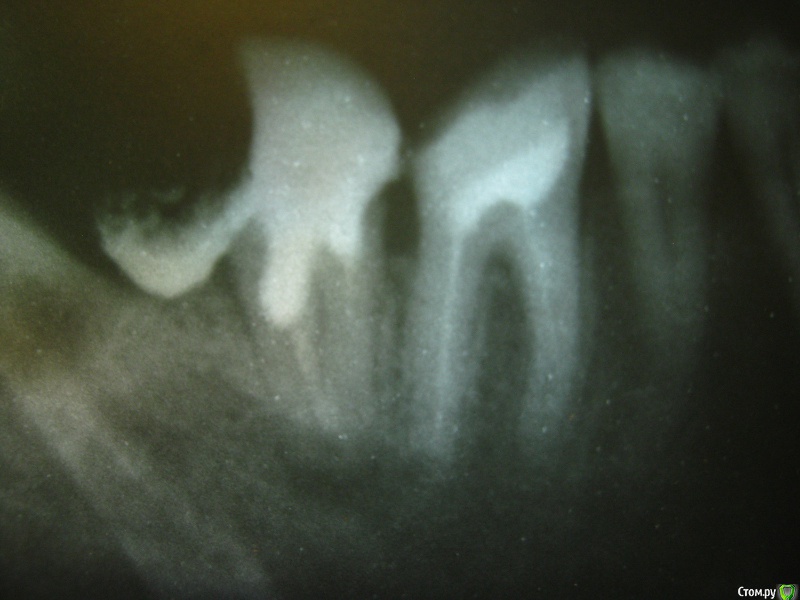

Katico Опубликовано 11 ноября, 2016 Поделиться Опубликовано 11 ноября, 2016 История началась с нижней лежачей восьмерки, которая упиралась в семерку. Семерка при этом не беспокоила. 8 сказали удалять, так как он уже был с кариесом и портил семерку. Удалила. Врач после удаления сказала, что 7 зуб надо переделать, так как он из-за 8 подгнил. (полтора года назад эта семерка была перелечена (не беспокоила, просто откололся маленький краешек ), пломбу поставили на штифты).После заживления лунки от 8 зуба я пошла переделывать 7. Там, где в него упирался 8 зуб была дыра и она затянулась десной. К сожалению не сделали снимок. Все это стали вскрывать, прижигали, долго сверлили, так как зуб сильно разрушился, искали видимо твердую ткань. Десна продолжала кровить, и врач сказала, что тут все плохо видно, что постоянную пломбу делать нет смысла, поставила временную и сказала, что скорее всего все заболит, щеку раздует и только на удаление. но если болеть не будет, то через неделю поставит постоянную.Я не хочу терять этот зуб и поэтому, когда он начал сильно болеть (через 2 дня) но щеку не раздуло, я не пошла на удаление. Сначала пила пенталгин, потом подключила доксициклин. антибиотик стал помогать. Я снова пришла к врачу стала требовать снимок, но она настаивала на удалении. снимок сделали. Она сказала, что киста и воспаление и нужно срочно удалять, прямо сейчас, убрала временную пломбу, но на удаление я не согласилась. Я ушла подумать. Пошла к другому врачу, которая мне ставила на него штифты, она тоже подтвердила удаление, но если после антибиотика успокоится, то может еще постоять, но переделывать, убирать штифты, лечить кисту, она не согласилась. по снимку вижу, что каналы пройдены не до конца, но она считает, что все правильно.Я поняла, что специалистов у нас нет, но зуб сохранить хочется. Подскажите, есть ли у него шансы? стоит ли искать специалиста в другом городе (ближе к нам Нижний Новгород)?И еще вопрос: что же так сильно болело? Неужели киста? или это просто воспаление, так как зуб побеспокоили и сверлили? и может ли антибиотик полностью воспаление убрать? и кроме этого еще возможно не все подгнившее убрали со стороны восьмерки, там же процесс продолжится, а сверху снова десной затянется. Как же тут быть?Очень переживаю за зуб, надеюсь на ваши советы. Ссылка на комментарий